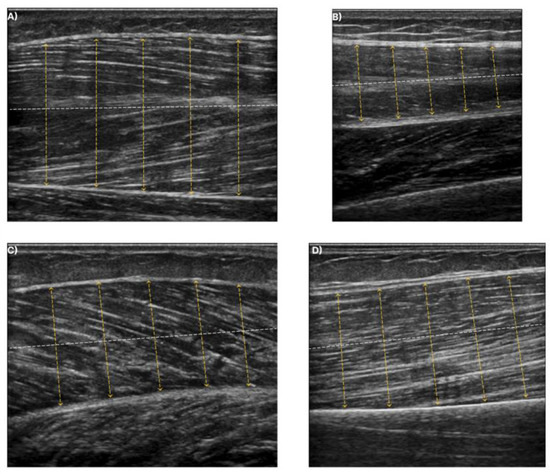

Additionally, in Figure 9, a sample of the predictions of the Gen Model is presented. From the segmented masks, it is clear that the synthetic images can be applied effectively for the delineation of the deep and superficial aponeuroses.

Figure 9. Qualitative results of the Gen Model in images of the four examined muscles. (A) T.A. muscle, (B) R.F. muscle, (C) GCM muscle, and (D) B.B. muscle.